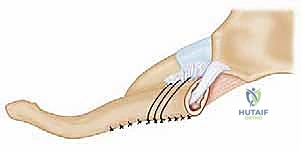

لا يمكن ببساطة خياطة الأربطة الممزقة لضمان الاستقرار. لذلك، يستخدم الدكتور هطيف تقنية متقدمة لإعادة البناء باستخدام "رقعة وترية" (Tendon Graft).

* أخذ الرقعة: غالباً ما تؤخذ من وتر العضلة الرشيقة (Gracilis) أو العضلة نصف الوترية (Semitendinosus) من ركبة المريض نفسه (Autograft)، أو استخدام رقعة صناعية طبية عالية الجودة.

* حفر الأنفاق العظمية: يتم حفر ثقوب دقيقة جداً في عظم الترقوة وعظم القص باستخدام أدوات جراحية متطورة.

5. تمرير الرقعة وتثبيتها (تقنية الرقم 8)

يتم تمرير الرقعة الوترية عبر الثقوب العظمية بنمط يشبه الرقم 8 (Figure-of-eight). هذه التقنية الميكانيكية الحيوية توفر قوة استقرار هائلة تحاكي قوة الأربطة الطبيعية (الرباط الكبسولي والرباط الضلعي الترقوي).